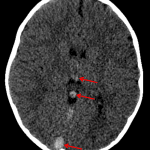

- High attenuation within the superior and posterior aspects of the superior sagittal sinus and in the straight sinus and bilateral internal cerebral veins

- Additional focus of high density near the left cerebellar tentorium

- Area of hypoattenuation in the right thalamus and genu of the right internal capsule

- Dural and deep venous sinus thrombosis

High attenuation within the superior and posterior aspects of the superior sagittal sinus and along the straight sinus and bilateral internal cerebral veins concerning for dural and deep venous sinus thrombosis. Additional focus of high density near the left cerebellar tentorium likely represents thrombus in the left transverse sinus. Recommend brain MRI with and without contrast for further evaluation.

Area of hypoattenuation in the right thalamus and genu of the right internal capsule is concerning for edema and possible developing venous infarct. This can also be assessed with MRI.

No acute hemorrhage, mass effect, or hydrocephalus.